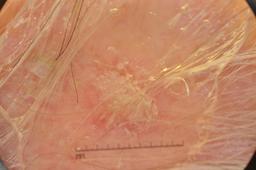

ISIC-DICM-17K (ISIC Dermoscopic Images and Clinical Metadata 17K) is a curated and balanced dataset derived from the International Skin Imaging Collaboration (ISIC) Archive Gallery. It comprises 17,060 dermoscopic images and clinical metadata (8,530 melanoma and 8,530 non-melanoma classes).

For more details, please follow the project’s GitHub repository: https://github.com/mmu-dermatology-research/isic-dicm-17k

This dataset was used in this study and benchmark to explore the effectiveness of multimodal learning for skin lesion classification:

S. Ahammed, X. Cui, W. Lu and M. H. Yap, "Skin Lesion Classification using Dermoscopic Images and Clinical Metadata: Insights from Multimodal Models," 2025 IEEE/CVF Conference on Computer Vision and Pattern Recognition Workshops (CVPRW), Nashville, TN, USA, 2025, pp. 222-230, DOI: 10.1109/CVPRW67362.2025.00027